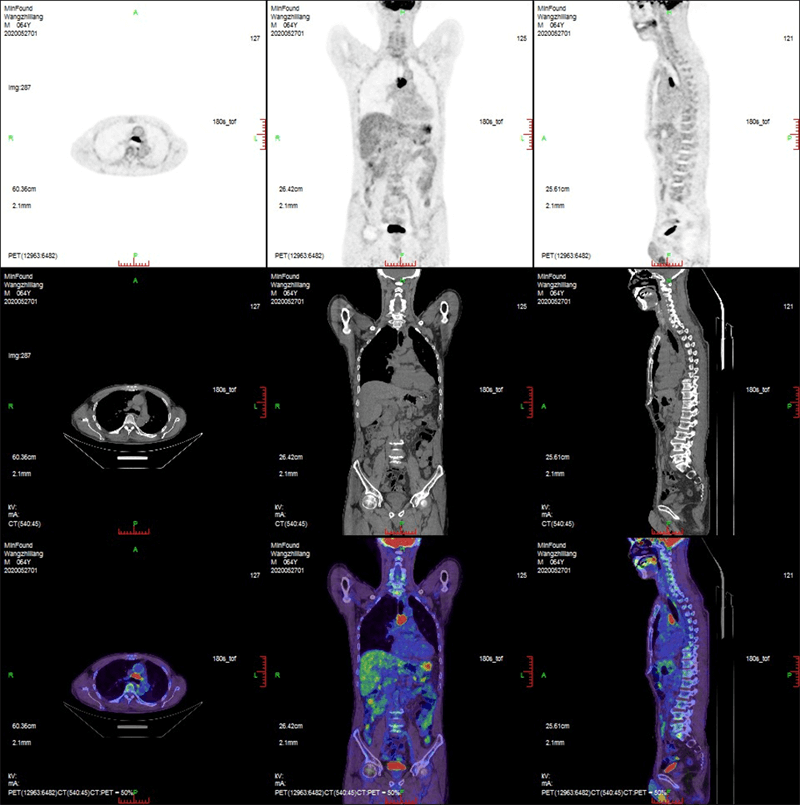

ScintCare PET/CT 720E uses the 4th-generation PET detector with which lutetium-yttrium oxyorthosilicate (LYSO) crystals are individually coupled to SiPM detectors without the optical conductor. This digital SiPM-based detector ensures 100% crystal coverage to the SiPM and greatly improves photons efficiency and images quality.

The 20.16 cm axial FOV compare to the conventional 16 cm axial FOV PET/CT, it speeds up the scanning process allowing greater patient throughput.

Respiratory gated PET/CTaims to eliminate the effects of motion artefact and provide a more accurate interpretation of pulmonary nodules and lymphadenopathy.

MinFound's digital gating technology is implemented directly, and can be set in the exam application. This technology not only saves additional preparation time, but also reduces overall examination duration.